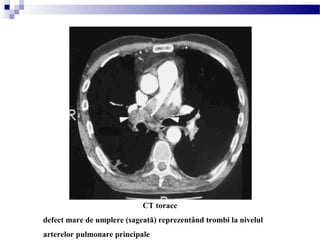

CT torace

defect mare de umplere (sageată) reprezentând trombi la nivelul

arterelor pulmonare principale